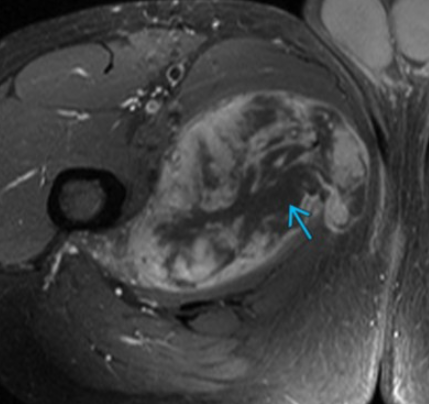

• Pelvic RMS

• Peak incidence in childhood at age ~2-6 years

• Can occur from anywhere including bladder, uterus, vagina, etc